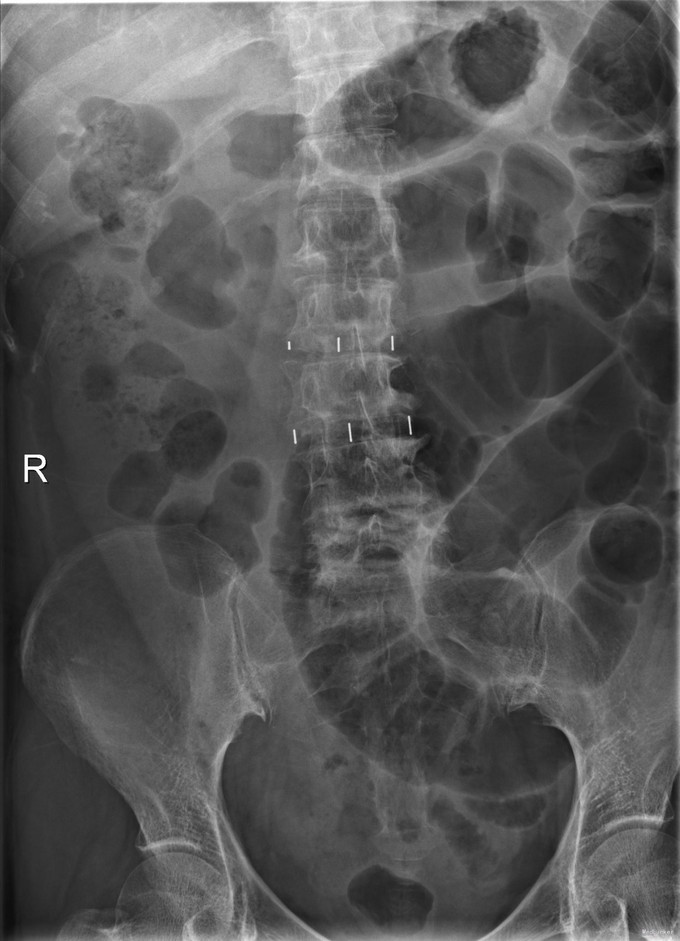

查体:脊柱无明显侧弯,腰背部无压痛,双下肢麻木酸痛,可牵连至脚跟。肌力肌张力可。腰部活动可,前屈后伸时感酸痛,无力。左侧直腿抬高试验阳性。 辅助检查:X线平片:腰椎侧弯前屈,L3椎体轻度滑脱,各椎间隙狭窄,腰椎退行性改变。 MRI:L4-5,L5-S1椎间盘膨出,L2-3,L3-4,L5-S1椎间隙狭窄,S2-3水平骶管内蛛网膜囊肿,腰椎序列不稳定,生理曲度局部后凸。

诊断:1 脊柱侧弯 伴不稳 2椎管狭窄 治疗: 前期微创腰椎侧路融合手术+后期 微创后路经皮内固定